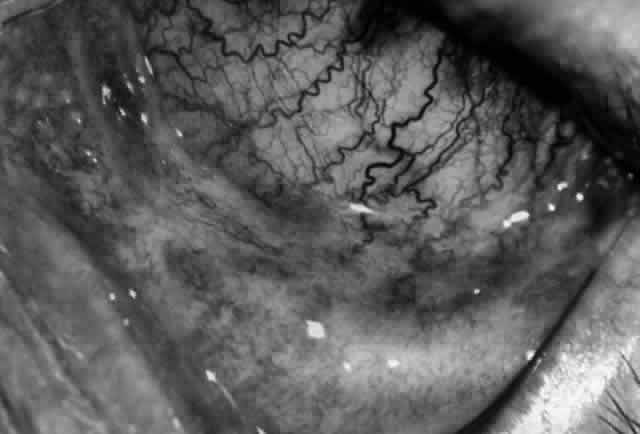

Clinically, the ocular disease in cicatricial pemphigoid (OCP) may present unilaterally in the form of a chronic, recurrent catarrhal conjunctivitis, but it eventually becomes bilateral. Subepithelial fibrosis is characteristic of stage 1 of OCP (Fig. 7). Stage 2 shows fornix foreshortening (Fig. 8), and symblepharon formation is the hallmark of stage 3 (Fig. 9). Stage 4, end-stage disease, is characterized by ankyloblepharon and surface keratinization (Fig. 10). Obstruction of the lacrimal ductules and meibomian gland ducts eventually produces an unstable tear film and progressive sicca syndrome, but it is to be emphasized that OCP is not a dry-eye syndrome until late in the disease course.20 Trichiasis and entropion occur because of the subepithelial fibrosis, with eventual keratopathy, corneal neovascularization, and corneal ulceration and scarring.20

Fig. 8. Stage 2 cicatricial pemphigoid, with fornix foreshortening and subepithelial fibrosis without frank symblepharon formation.